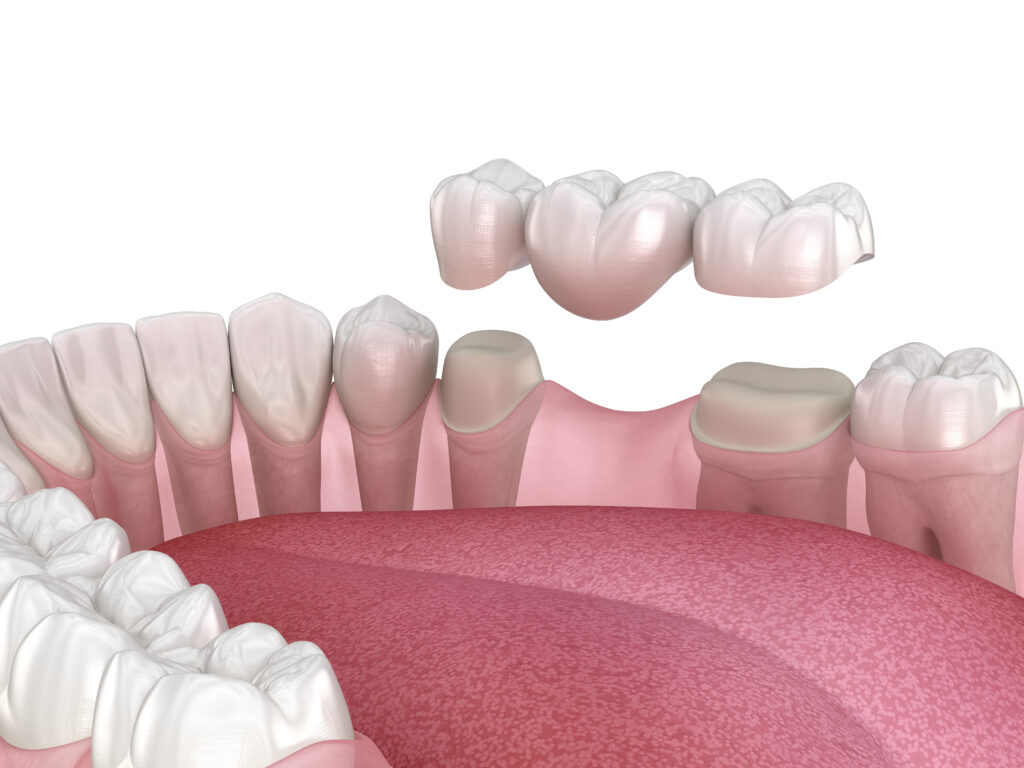

ブリッジ(保険適応・保険適応外)

失った歯と隣り合う歯を土台にして、歯のない箇所に人口の歯の「橋」を渡す方法です。